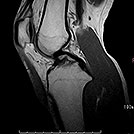

MRI画像

膝関節T2強調像

膝関節T1強調像

- 四肢関節の断層撮影(靭帯損傷・断裂の診断など)